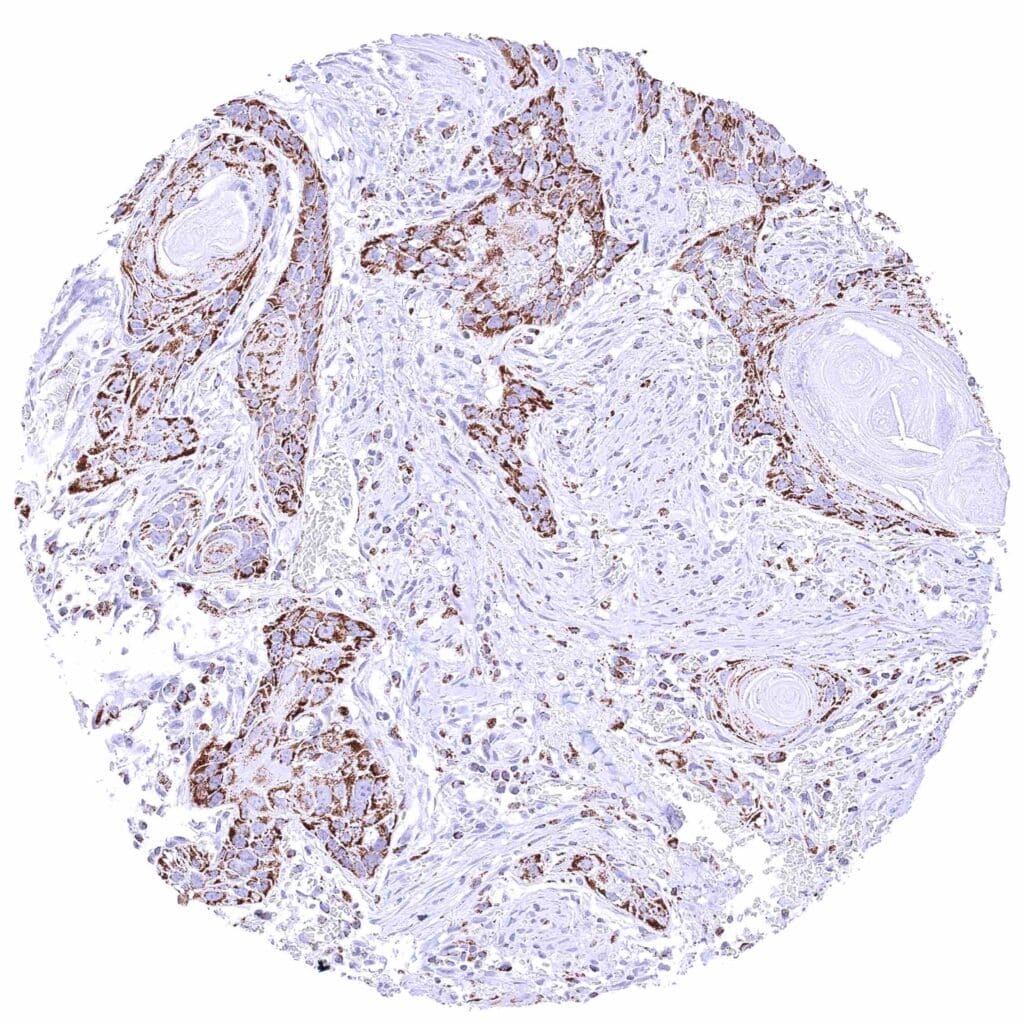

Uterus, cervix – Squamous cell carcinoma with moderate to strong cytoplasmic ATP5J staining of tumor cells.